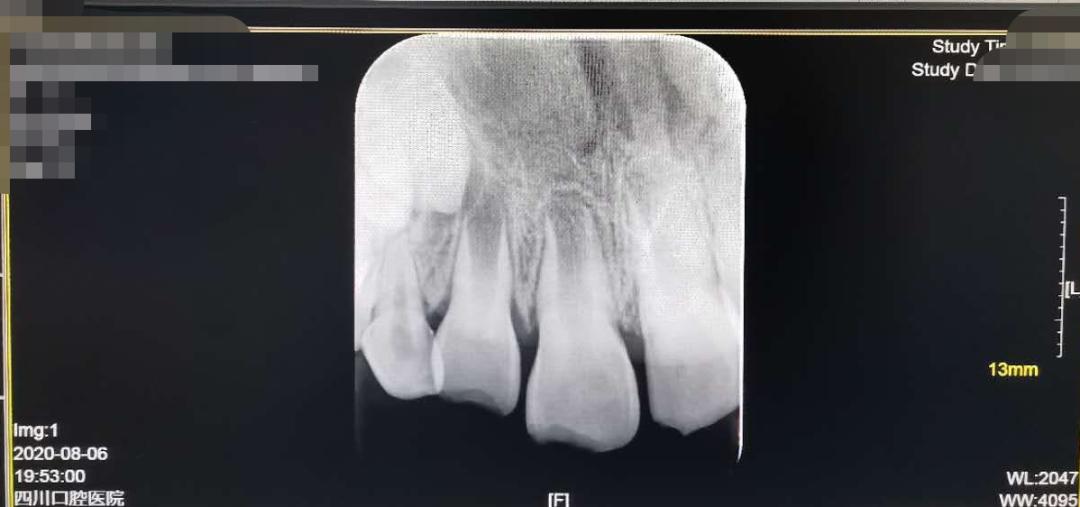

在四川口腔医院8月6日出具的病历中,记者看到,孩子的检查结果为:下唇挫伤、11牙、12牙牙本质折断未露髓,21牙牙釉质折裂。医院建议,应定期复查拍片观察压根发育情况,若出现疼痛、变色等不适症状需及时就诊。